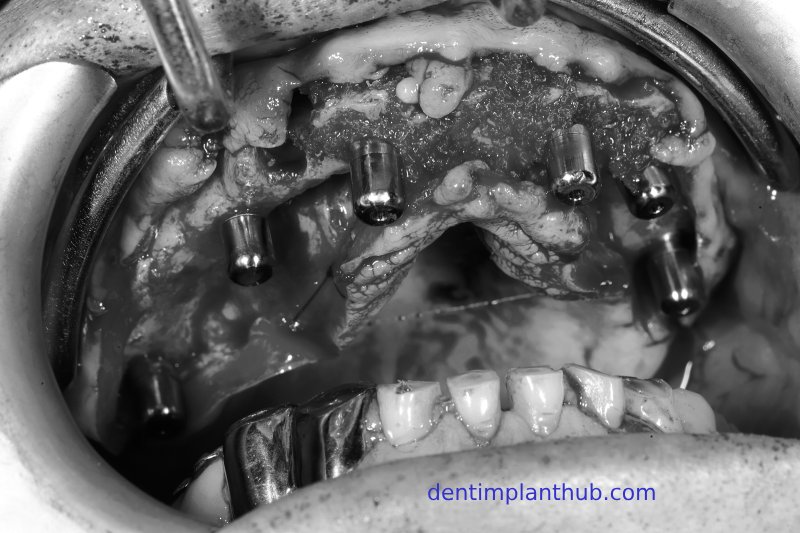

Photos taken during the implant surgery

The surgery was conducted on Wednesday, August 3rd, 2022, at 8:30 a.m. - For tooth 12, the implant model is 3612. - For tooth 14, the implant model is 4010, with 1 pack (0.25 grams) of bone powder and 1 piece of collagen sponge. - For tooth 18, the implant model is 4510, implanted at an inclination. - For tooth 22, the implant model is 3612. - For tooth 24, the implant model is 4010. - For tooth 26, the implant model is 5010, with internal maxillary sinus lift, and 1 pack (0.25 grams) of bone powder. - For tooth 45, the implant model is 4510. - For tooth 46, the implant model is 4510. - For tooth 36, the implant model is 4510, with immediate implant placement, and 1 pack (0.25 grams) of bone powder.